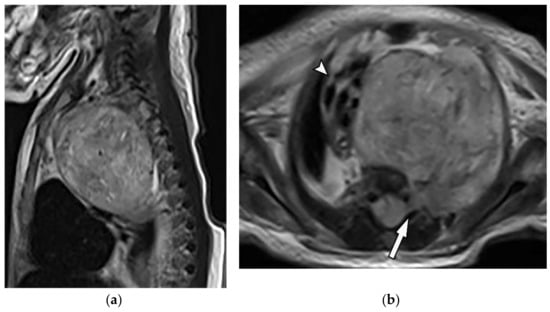

12.1. Rhabdomyosarcoma

Rhabdomyosarcoma is a high-grade sarcoma that mostly affects children and usually appears before 40. Chest wall rhabdomyosarcomas are uncommon tumors with poor prognosis and usually manifest as rapidly growing mass with adjacent bone invasion and nerve compression [1,16].

CT scan demonstrates homogenous mass with no mineralized matrix invading adjacent bone and soft tissue structures (Figure 29) [16]. MRI is the modality of choice for better delineation of tissue characterization, tumor extension, and medullary involvement. It is isointense to muscle on T1-weighted and hyperintense on T2-weighted images. Typical homogenous or ring-like enhancements are expected. Non-enhanced areas of hypointensity are reflective of necrosis (Table 3) [1,16,60]. 18F-FDG PET/CT is valuable in the primary staging, restaging, prognosis, and therapeutic assessment [61].

Figure 29.

A 5-year-old girl with dyspnea. The axial contrast-enhanced CT in soft tissue window was obtained at the level of the main pulmonary artery (a,b), showing a large infiltrative soft tissue mass (arrow) with irregular border and slight enhancement encasing great mediastinal vessels. Left-sided pleural effusion was also identified. Coronal (c) and sagittal (d) CT better delineate the extension of the tumor and demonstrates infiltrative soft tissue mass within the superior, mid, and posterior mediastinum extending to the thoracic inlet and neck.